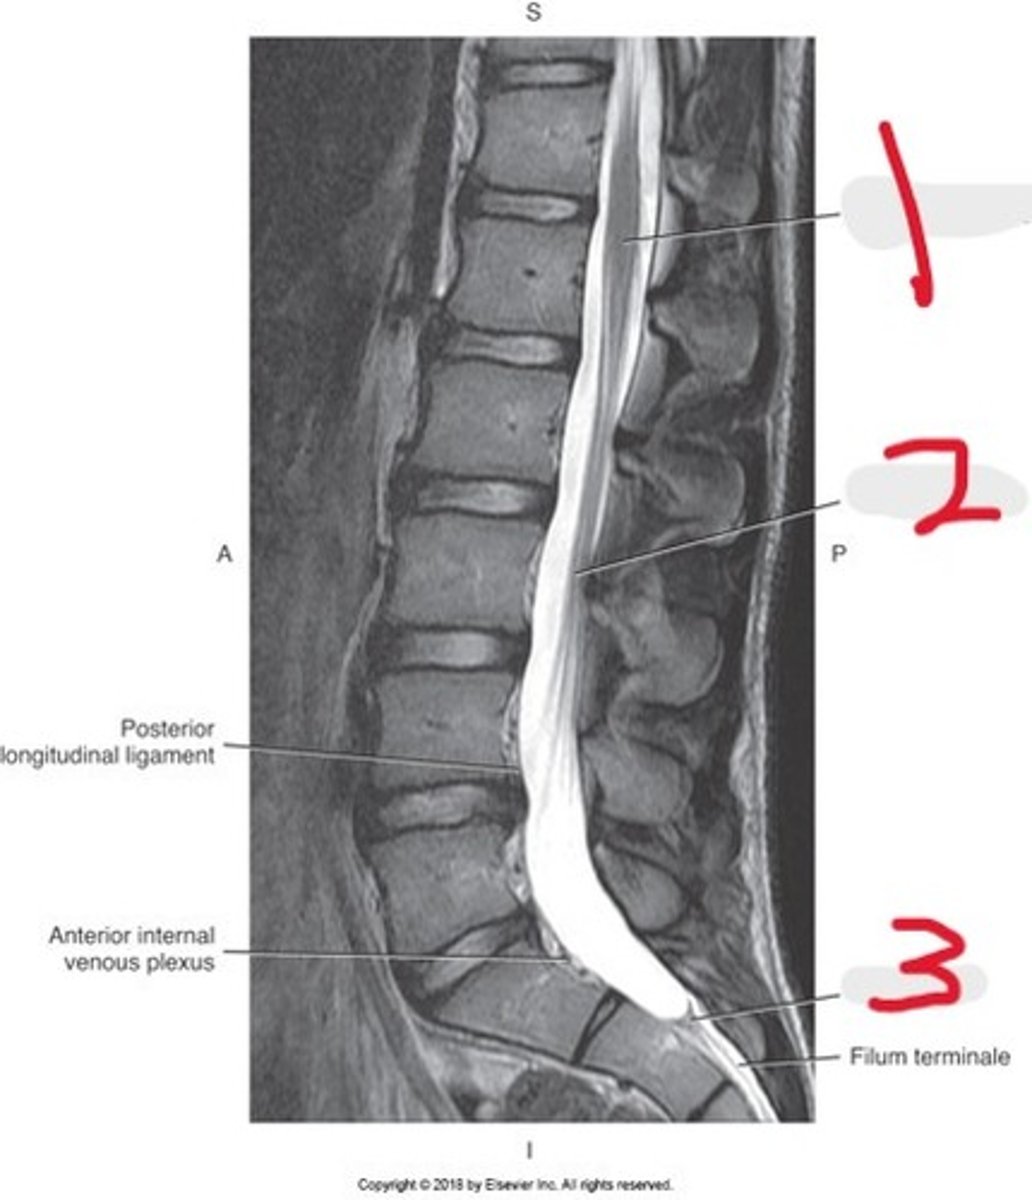

1) Conus medullaris

2) Cauda equina

3) Thecal sac

Name all numbered structures